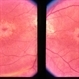

- macular dystrophy, color fundus photograph

Scanning laser ophthalmoscope

Mirante - Description

- Fundus photographs of BE of a 48 year old male with macular dystrophy